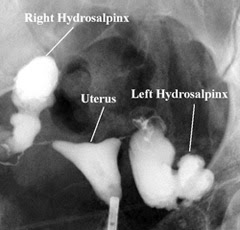

In a woman with hydrosalpinx, the fallopian tubes look like sausages, like the picture below.

![]() |

| Woman with Hydrosalpinx |

My left side looked completely normal. My right side – nothing. You couldn’t even see the hydrosalpinx. The tube was completely blocked all the way from the entrance from the uterus. The radiologist said, “As you can see, your right side is completely blocked. The way it’s blocked however is not indicative of hydrosalpinx because it usually occurs on both sides, however what I see here would certainly cause fertility trouble. I’ll send my report to Dr. Bean and he’ll follow-up.”